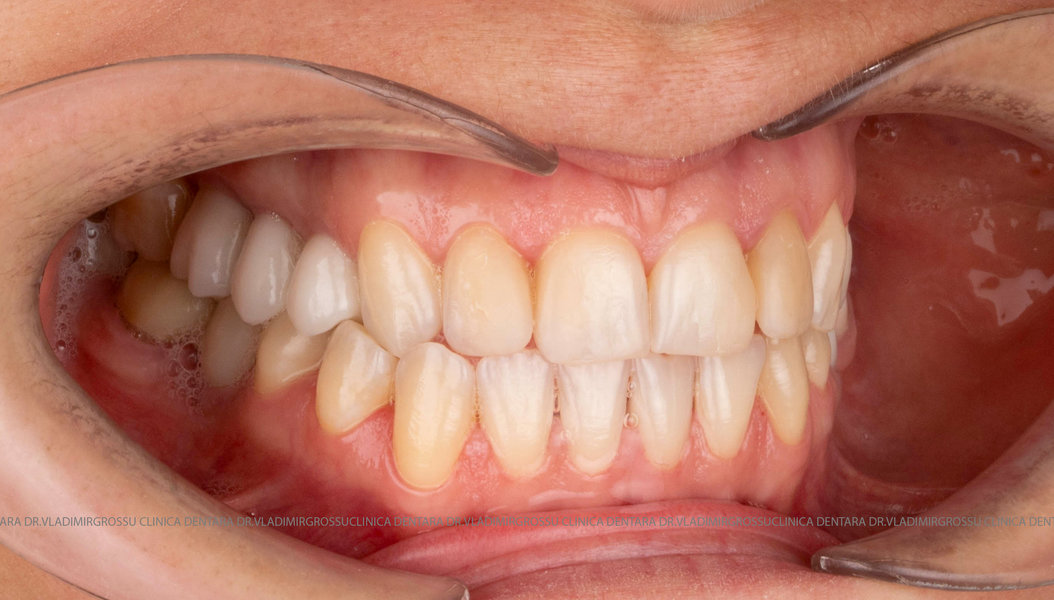

Caz 1

Transformările estetice și impactul reabilitării asupra vieții pacienților

Reabilitarea dentară produce o schimbare vizibilă și profundă în aspectul pacientului, cu efecte pozitive evidente asupra stimei de sine și a calității vieții. Mulți pacienți relatează bucuria redobândirii funcției masticatorii și dispariția complexelor legate de aspectul dentar.